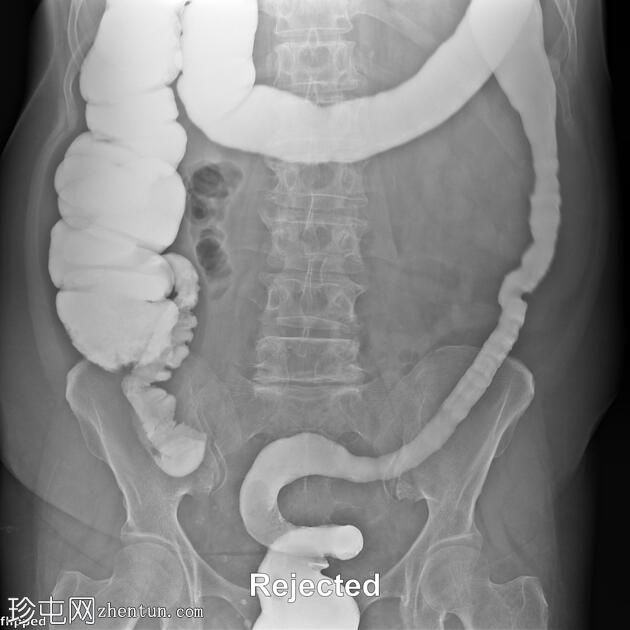

结肠异常表现包括结肠袋皱襞消失,使其外观模糊,呈铅管样改变。

其他异常表现包括降结肠和乙状结肠肠袢狭窄,以及横结肠和降结肠多处黏膜糜烂(双对比增强图像可见)。

未见肿块或瘘管形成。

升结肠外观正常,结肠袋皱襞完整。

结肠呈铅管状外观是慢性炎症性肠病(溃疡性结肠炎)的典型放射学表现。